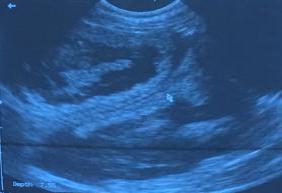

On January 30th I will have an USG done to confirm the pregnancy

January 30, 2016   We have a confirmed pregnancy       puppies due around March 2nd.